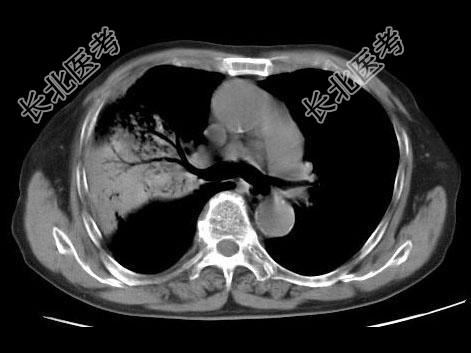

- 单项选择题男,23岁, 高热,咳铁锈色痰, 胸部CT扫描如图,最可能的诊断为 ( )

A、右上肺干酪性肺炎

B、右上肺金葡菌肺炎

C、右上肺大叶性肺炎

D、右上肺中央型肺癌

E、右上肺肺结核